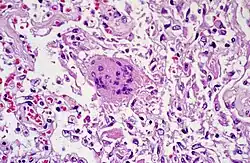

Fremdkörper-Riesenzellen bei Aspirationspneumonie, Autopsiepräparat, H&E.

Riesenzelle und diffuser Alveolarschaden bei SARS-Infektion.